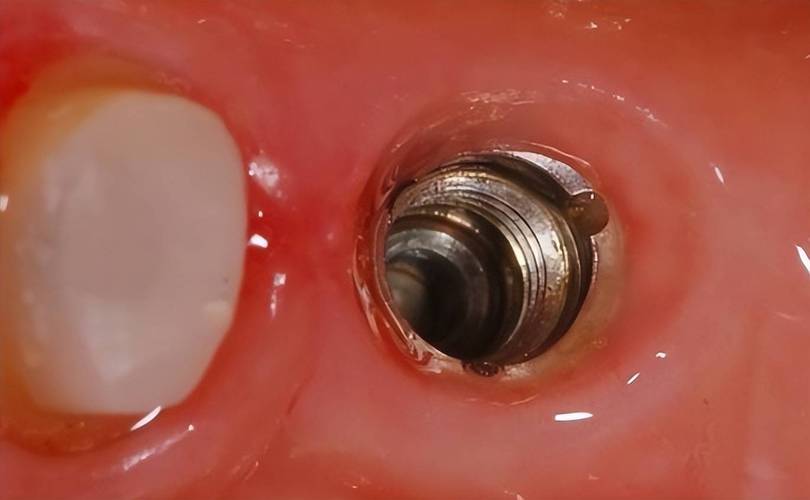

植入种植体:

- 当窝洞预备完成后,医生将纯钛或钛合金制成的种植体(通常带有螺纹)旋入或敲入预备好的窝洞中。

- 关键要求:

- 初期稳定性: 种植体植入后必须获得良好的初期稳定性,这是骨结合成功的基础,医生会通过手感、敲击声音或扭矩扳手确认稳定性。

- 深度: 种植体植入的深度需达到预设的生物学宽度要求,并确保植入位置正确(通常平台位于牙槽嵴顶或略低于骨面)。

- 方向: 与备洞方向一致,符合最终修复设计。

二期手术(如埋入式愈合):

- 如果种植体是埋入式愈合,需要在骨结合完成后,做一个小切口,暴露种植体上方的愈合基台。

- 愈合基台的作用是引导牙龈形成良好的袖口形态,为后续修复体提供入口。